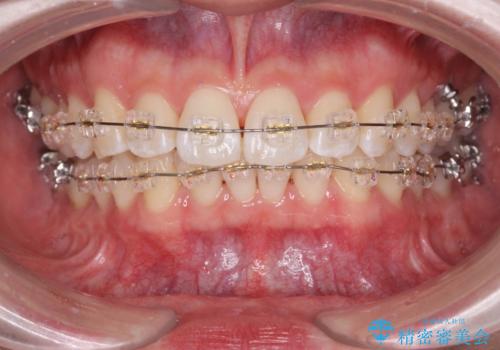

- 前歯のガタつき、突出感のある前歯の改善を求めて来院されました。

前歯の角度を改善し審美性を高めるとともに、奥歯のガタつきも並べ直すことで安定した咬合関係の確立を目指します。

歯列の側方拡大をしっかりと行ったことで歯を抜かずに前歯の角度をしっかりと改善することができました。